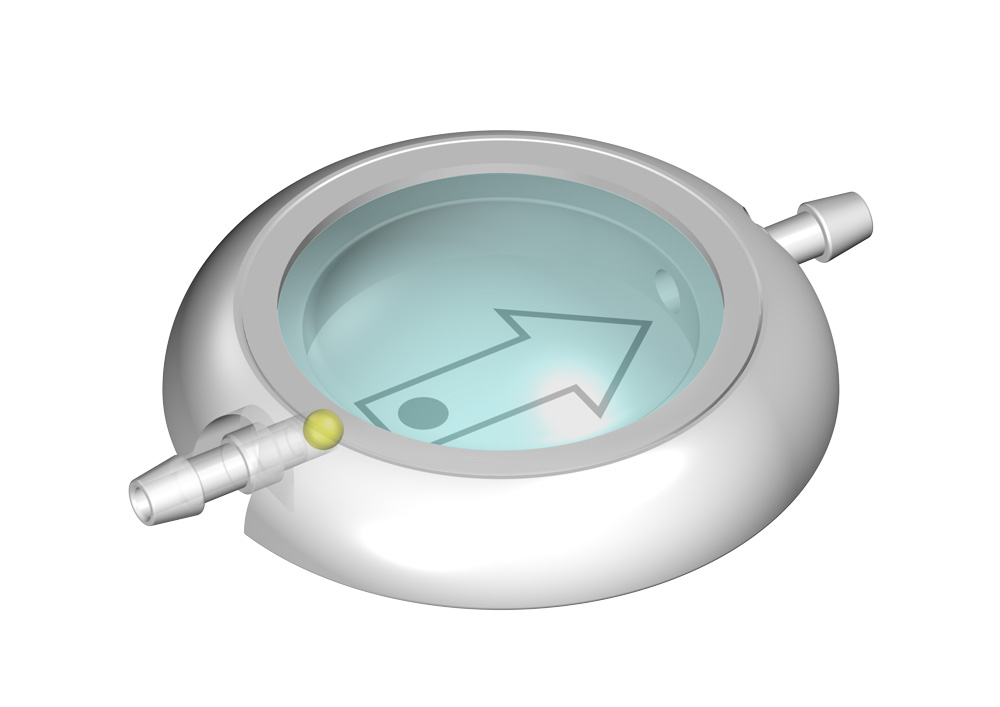

MIETHKE Vorkammern

Ein solches CONTROL RESERVOIR bzw. eine Vorkammer ermöglicht die Messung des intraventrikulären Drucks, die Injizierung von Medikamenten und ggf. eine Ventilkontrolle. Eine Entnahme von Liqour und Zugabe von Medikamenten kann durch die Punktion der Silikonmembran mit einer Kanüle erfolgen. Der solide Titanboden verhindert dabei das Durchstechen mit einer Kanüle.

Alle MIETHKE CONTROL RESERVOIRE und Vorkammern sind gut erkennbar im Röntgenbild und bedingt MR sicher, d.h. Kernspinresonanzuntersuchungen (MR) oder computertomographische Untersuchungen (CT) können ohne Beeinträchtigung des Patienten durchgeführt werden.

Die Reservoire sind für Katheter mit einem Innendurchmesser von ca. 1,2 mm und einem Außendurchmesser von ca. 2,5 mm ausgelegt (außer LP-Vorkammer).